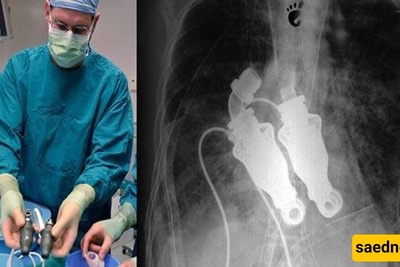

Osteoporosis, a condition that leads to weakened bones and an increased risk of fractures, affects more women than men, primarily due to declining estrogen levels. However, men can also develop osteoporosis, often without being properly diagnosed, which can lead to serious complications later on. It’s essential for both men and women to be aware of their bone health and seek guidance from healthcare professionals, such as those at Sarvodaya Hospital in Faridabad.